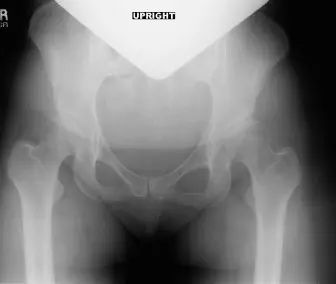

الأشعة السينية العادية Plain Radiographs

هي الخطوة الأولى والأكثر أهمية. تُظهر صور الأشعة السينية معالم عظمية رئيسية وتوفر قياسات حاسمة:

زاوية مركز الحافة الجانبية (Lateral Center-Edge Angle - LCEA) لوبرغ:

تقيس مدى تغطية الحُق لرأس الفخذ من الجانب. القيمة الطبيعية أكبر من 25 درجة. إذا كانت أقل من 20-25 درجة (كما في حالة المريضة التي كانت 12 درجة)، فهذا يشير بوضوح إلى خلل التنسج.

زاوية تونس (Tönnis Angle - Acetabular Index):

تقيس ميل الحُق. القيمة الطبيعية أقل من 10 درجات. إذا كانت أكبر من 10 درجات (كما في حالة المريضة التي كانت 20 درجة)، فهذا يشير إلى انحدار الحُق ونقص التغطية العلوية.

مؤشر بروز رأس الفخذ (Femoral Head Extrusion Index):

يقيس نسبة رأس الفخذ التي لا يغطيها الحُق. القيمة الطبيعية أقل من 25%. إذا كانت أعلى (كما في حالة المريضة التي كانت 35%)، فهذا يؤكد عدم كفاية التغطية.

خط شنتون (Shenton's Line):